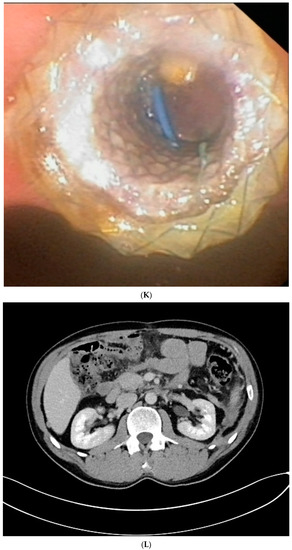

Figure 1. (A–L) Endoscopic treatment of walled-off pancreatic necrosis. In the second week of acute necrotizing pancreatitis, the acute necrotic collection (A) is visible in the abdominal contrast-enhanced computed tomography (CECT), which evolved in the sixth week of the illness duration into the symptomatic walled-off pancreatic necrosis (B). Patient qualified for endoscopic treatment (C–F) transmural drainage using the self-expanding metal stent (C,D) and endoscopic necrosectomy (E,F) was performed. In the second week of endotherapy, the endoscopic retrograde pancreatography (G–J) was performed. During pancreatography, the complete pancreatic duct disruption was stated (G–I) and transpapillary drainage was carried out (J). After achieving the treatment’s success and the complete regression of the necrotic collection, the transpapillary stent was observed in the bottom of the collection via the endoscopic view from the stomach’s side through the transmural stent (K). Control CECT confirmed the total regression of the collection (L).